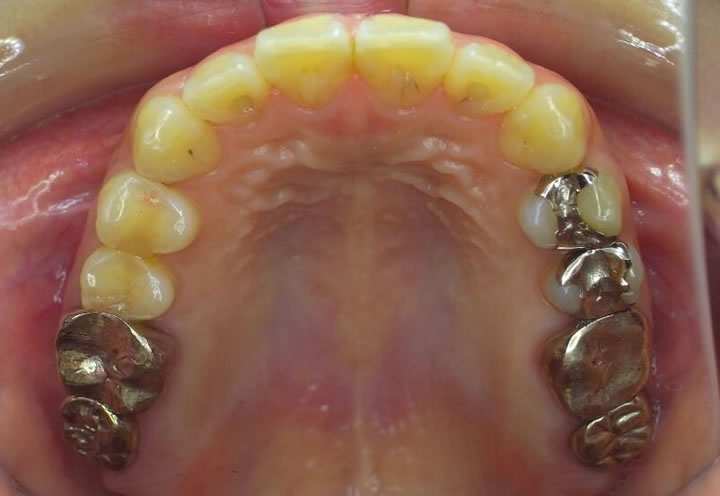

主訴:左上の銀歯脱離

口腔内所見:縁下カリエスと頬側の歯牙破折をきたしており保存不可と診断

抜歯で同意しその後の治療においては、①ブリッジ②入れ歯③インプラント④移植⑤その他(放置など)それぞれのメリット、デメリットをお話し理解していただきました。

今回のケースでは親知らずが残存しており、移植を保険内で行うことができます。また移植が成功すれば、自分の歯として違和感なく使えるという大きなメリットがあるため移植を選択されました。